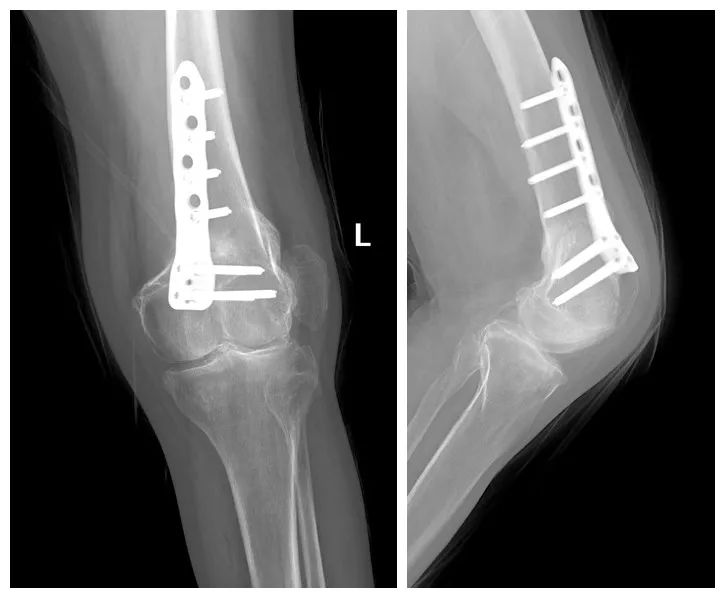

双膝关节 X 线片示:

右膝外翻畸形,截骨矫形术后,右侧股骨下端断端对位、对线良好,骨折线尚较清楚。内固定钢板及螺钉未见松动、断裂。右侧髌骨完全脱位,偏向外侧,髌骨关节面粗糙。

左膝外翻畸形截骨矫形术后:内固定器在位良好,骨折断端可见骨痂及愈合征象,髌骨位于股骨外前方,股胫外侧间隙变窄,股骨下角约 83°。